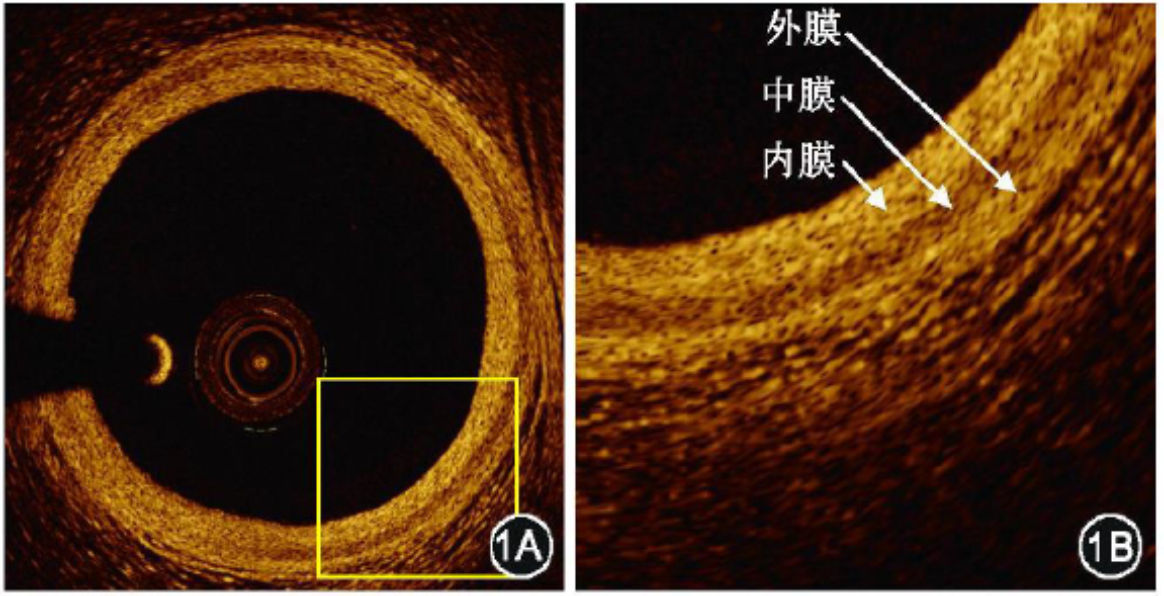

与此同时,由于其与病理组织学图像具有良好的对应性,可在近似于组织学水平上诊断和评价冠状动脉斑块,从而让我们更好地理解冠状动脉疾病的病理学特点,并针对不同患者的自身特点进行个体化治疗,如图1。

图1 冠状动脉三层结构;OCT能清楚区分血管三层结构;IVUS则不能准确区分血管内膜和中膜的界限

4. 正常冠脉三层结构(图4)

内膜:主要由弹力纤维构成,高信号的亮带状(高背散,亮度高,质地均一、细腻);

中膜:主要由平滑肌细胞构成,信号较低的暗带(低背散、亮度低、疏松);

外膜:主要由外弹力膜和细胞外基质构成,信号较强但不均一的亮带(亮度高但质地不均一)。

简单来说完整的的三层结构为“亮-暗-亮”。

图4 OCT图像冠脉的三层结构(1B为1A中方块的放大图)